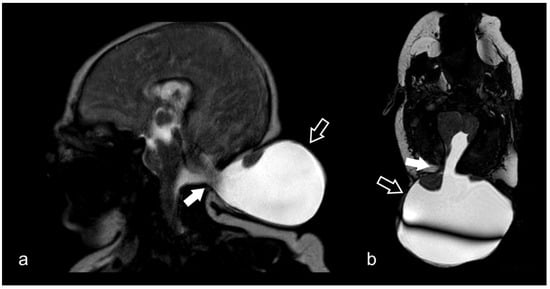

3.10. Cranio-Cervical Malformations (Chiari I)

3.12. Neonatal and Fetal MRI